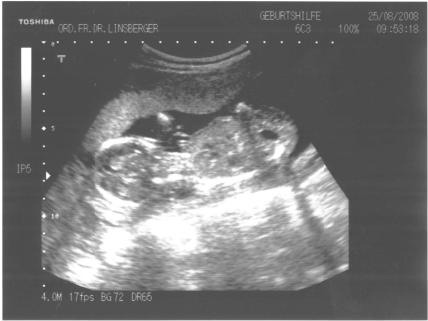

18. Schwangerschaftswoche:

Ultraschall in Oesterreich